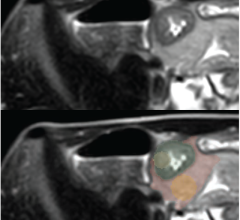

November 30, 2023 — Youth baseball players are prone to elbow pain and injuries, including repetitive overuse changes ...

November 29, 2023 — Using artificial intelligence (AI) to analyze specialized brain MRI scans of adolescents with and ...

November 21, 2023 — A newly developed artificial intelligence (AI) system that analyzes specialized MRIs of the brain ...